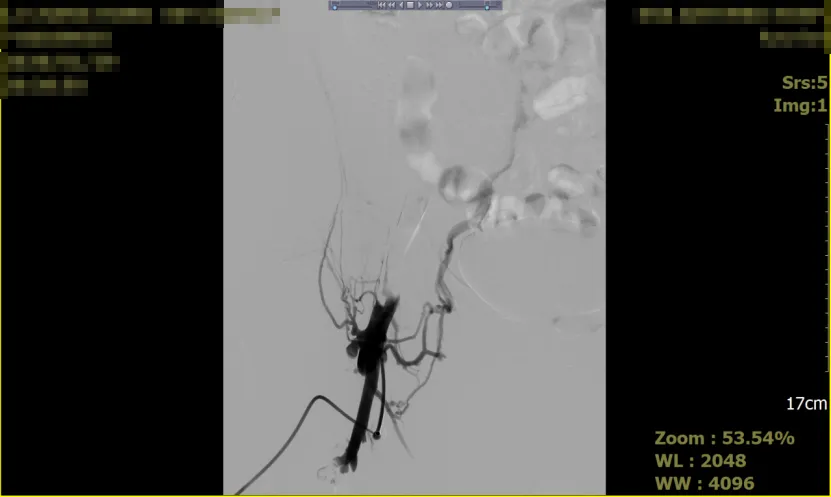

2025-10-112020年,全球的胃癌死亡病例为768793例[1],位居于所有癌症死亡谱的第四位,造成胃癌患者死亡的主要原因是复发和转移。其中,腹膜是胃癌最常见的转移部位,根据数据统计,70%的胃癌患者在手术后出现了腹膜转移[2],晚期胃癌的腹膜转移率可能更高。图片来源:freepik 胃癌是怎么转移到腹膜的呢?腹膜是腹腔里覆盖在腹壁内面和脏器外面的一层膜状组织,负责分泌黏液减轻内脏之间的相互摩擦,起着保护内脏的作用。腹膜本身就覆盖于胃的表面,胃壁的血管、淋巴管都经过腹膜与外界相连。因此,胃癌细胞能通过直接侵犯、血行转移、淋巴转移或种植途径到达腹膜,并在适宜的条件下“生根发芽”。由于胃壁的固有肌层中穿行着大量的淋巴管和血管,即使是早期的胃癌(T2期,侵犯固有肌层)也可能腹膜转移,多项回顾性研究中结论都表明:那些经过根治性治疗后却在短时间内出现转移的,很大一部分原因是在根治术之前没有发现已经存在的腹膜转移。图片来源:freepik胃癌腹膜转移如何早发现呢?早发现早治疗是所有疾病诊疗的最优解!对于腹膜转移的一些早期表现应该引起我们的足够重视!1、腹胀早期的腹膜转移一般不会出现明显的肿块,而会出现一些类如腹胀之类的非特异性表现,这时我们需要观察腹胀症状与饮食、排便、体位等的关系,如果是一过性出现的(如排便后缓解),则可能与消化不良等情况有关,如果持续不缓解、甚至进行性加重,则要引起高度重视,尽快就医检查。2、腹水在发生腹膜转移后,形成广泛的癌结节或腹腔游离癌细胞,影响腹膜本身的淋巴、血液运行,导致血管通透性增加、腹膜炎症发生、淋巴回流障碍以及低蛋白血症等,从而促进癌性腹水生成。据统计,由腹膜转移而引起的癌性腹水发生率高达90%,且预后不良,平均生存期仅12-20周[3]。不过,即使检查发现有少量腹水,也很难确认有没有腹膜转移,因为其他疾病也可能引起少量腹水(如低蛋白血症、腹膜炎症等)。 胃癌腹膜转移如何诊断呢?目前,确诊腹膜转移的方法有两种,一种是腹腔灌洗液/腹水的细胞学检查,一种是诊断性腹腔镜探查。很多腹膜转移是在准备进行胃癌根治术前,通过腹腔镜探查发现的。根据检查结果,腹膜转移又被分为“腹腔游离癌细胞阳性”和“肉眼可见腹膜转移”两种类型。图片来源:freepik1、腹腔游离癌细胞阳性:就是在腹腔灌洗液、腹水等检查中找到了胃癌细胞,但没有发现肉眼可见的腹膜转移灶结节。2、肉眼可见腹膜转移:腹腔镜或者影像学明确腹膜转移灶,如CT发现腹膜上呈饼状的结节,增强后明显强化,可伴有腹水四 胃癌腹膜转移如何治疗呢?随着肿瘤治疗理念的进步,很多单一转移或寡转移的病灶可以通过转化治疗等新的治疗方式来取得临床治愈的效果,例如结直肠癌肠癌单一肝转移等。但在腹膜转移中,由于腹膜范围广泛、局部处理难度极大,因此很难将腹膜转移视为单一部位转移,手术治疗仅在少数患者中进行且争议较大。针对不同的腹膜转移类型,进行分层管理诊疗,是目前胃癌腹膜转移的主要治疗手段,包括腹腔化疗港置入、腹腔热灌注及新辅助/转化治疗等,明确改善了患者预后。图片来源:freepik1、仅有腹腔游离癌细胞阳性(CY1P0)就是在完善检查后,只发现腹腔游离癌细胞阳性,没有肉眼可见的转移灶。从技术上来说,CY1P0的腹膜转移是可以做根治性切除的。不过,人们发现单纯切除腹膜并不能提高这部分患者的生存率(生物学上不可切除)。因此,目前CY1P0的治疗仍是以系统性为基础,原发灶(胃)手术联合前/中/后腹腔热/灌注/化疗等综合治疗模式。术前治疗:Meta分析结果显示,共计6499例胃癌腹膜转移患者中,进行术前治疗并在术前腹腔细胞学转为阴性的患者的生存时间明显延长,术前治疗包括化疗、腹腔灌注等[4]。手术治疗:除非有明显的局部症状(出血、疼痛等),考虑到腹膜切除的难度,一般CY1P0的手术只有在腹腔细胞学完全转阴后才做考虑。术中腹腔灌注:就是把化疗药直接灌倒腹腔内,通过与腹膜充分接触发挥细胞毒作用。荟萃分析显示,手术联合腹腔化疗/广泛灌洗可以提高5年生存率、降低复发率。术后治疗:CCOG0301研究指出[5]:CY1P0术后替吉奥单药辅助化疗,患者的平均生存时间达22.3个月。 2、仅有肉眼腹膜转移(P1)单纯肉眼腹膜转移的患者,就算是化疗起到缩小转移灶的效果,手术完全切掉肉眼转移灶后,仍然有大部分人出现腹腔内复发。因此,对于P1胃癌的治疗,以全身治疗(化疗)为主,配合腹腔灌注治疗。只有在腹膜转移灶化疗效果好时,才考虑手术治疗,这种手术又被称为“肿瘤细胞减灭术”。研究显示:化疗后进行肿瘤细胞减灭术的患者生存时间长于没有手术者。 3、肉眼腹膜转移伴其他脏器转移以姑息性治疗为主,对有腹胀、腹水等症状的腹膜转移,可以考虑腹腔灌注及腹水引流,局部症状严重(如出血、梗阻等)时可以考虑姑息性手术治疗。只有极少数经过严格筛选的、对转化化疗反应好的患者有可能获得根治性切除的机会。 文末小结胃癌一旦发生腹膜转移,理论上来说就已经属于晚期了,其治疗还是应该以全身性药物治疗为基石、腹腔局部治疗为补充,手术治疗需要经过医生严格的评估后才考虑。参考文献:[1]闫超,陕飞,李子禹.2020年全球胃癌负担分析:聚焦中国流行现状[J],中国肿瘤.2023,32(03):161-170.[2]预防性腹腔热灌注治疗应用于进展期胃癌术后的研究进展[J],世界最新医学信息文摘.2020,20(85):109-111.[3]金春英,荆丽莉.腹腔热灌注化疗联合静脉化疗治疗胃癌性恶性腹水的临床疗效分析[J],临床研究.2017,15(18):160.[4]张俊.胃癌腹膜转移诊治的立与破[R].北京:2024CSCO胃癌专家委员会学术年会,2024.[5]CCOG0301研究组.单纯腹腔游离细胞学阳性的胃癌患者行常规D2手术及术后辅助S-1化疗的Ⅱ期单臂研究[R].北京:中国临床肿瘤学会,2015.